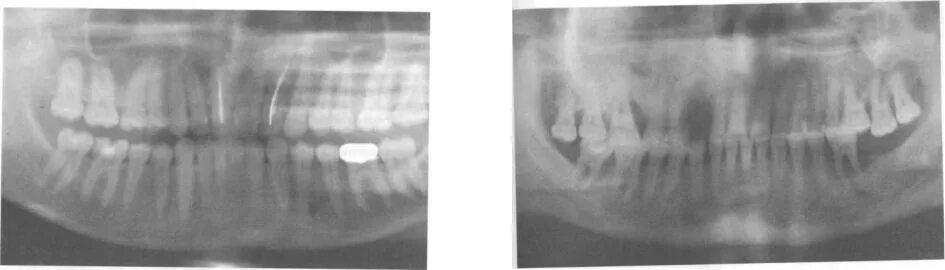

Признаки резорбции